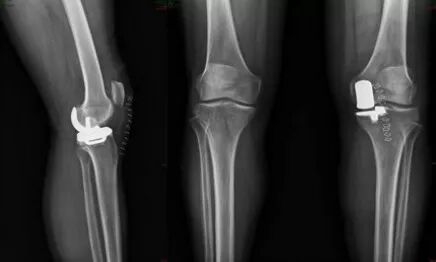

患者楊女士,3年前開始出現(xiàn)左膝關(guān)節(jié)疼痛,不能上下樓梯,疼痛難忍,日?;顒?dòng)受到限制,診斷為“左膝關(guān)節(jié)骨關(guān)節(jié)炎”,就診于省級(jí)知名骨科專家、邦爾骨科集團(tuán)首席專家、嘉興邦爾骨科醫(yī)院院長(zhǎng)趙凱教授專家門診。經(jīng)趙凱教授為其診查后,發(fā)現(xiàn)患者膝關(guān)節(jié)病變局限于內(nèi)側(cè)髁,非常適合做“微創(chuàng)單髁膝關(guān)節(jié)置換術(shù)”,并且手術(shù)創(chuàng)傷小,術(shù)中無出血,術(shù)后恢復(fù)快。手術(shù)過程很順利,術(shù)后第5天患者不用拄拐就可下床活動(dòng),回歸到正常生活。

這種微創(chuàng)膝關(guān)節(jié)置換,相比于傳統(tǒng)膝關(guān)節(jié)置換手術(shù),術(shù)中無出血,感染率低,術(shù)后恢復(fù)更快,無皮下淤血瘀斑,膝關(guān)節(jié)活動(dòng)度更加良好。

術(shù)前檢查顯示患者左側(cè)膝關(guān)節(jié)骨性關(guān)節(jié)炎,病變僅限于內(nèi)側(cè)髁

術(shù)后顯示假體位置良好